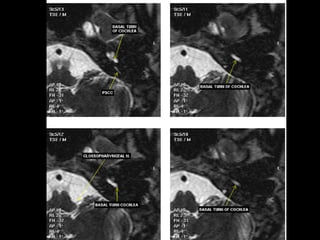

Anterior tympanic level TheTM may be identified as a thin filamentous structure extending from the scutum superiorly and coursing parallel to the plane of the long process of the malleus to attach to the limbus inferiorly. The head and neck of the malleus can be seen in the epitympanic space, with the tendon of the tensor tympani muscle attaching to neck. The labyrinthine and tympanic segments of the facial nerve are seen as two lucencies superior to the cochlea. Midtympanic level This level shows the long process and lenticular process of the incus and the incudostapedial articulation as an L- shaped configuration. Prussak’s space is seen between the incus and scutum. The tympanic segment of the facial nerve canal is seen along the medial wall of the middle ear just superior and lateral to the cochlea.

• 127.

Oval window level Thefull extent of the IAC is well visualized at this level, with the central crista falciformis dividing the canal into two portions. Oval window is seen as a bony defect in the lateral portion of the vestibule. Beneath the lateral SCC, the horizontal portion of the facial nerve canal appears as a small circular structure. The epitympanic space lies just lateral to the lateral SCC. Posterior tympanic level  The facial nerve recess is lateral to and the sinus tympani medial to the pyramidal eminence.  The round window niche is seen along the basal turn of the cochlea.